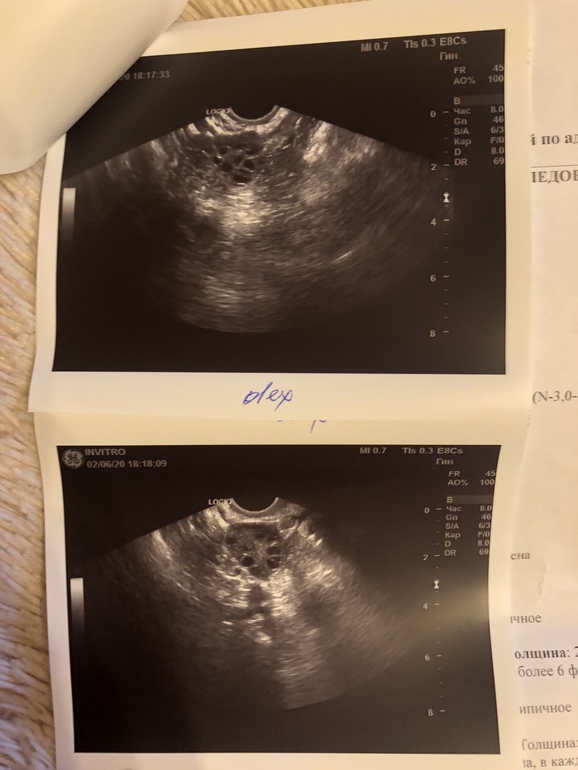

Пришла на узи на 25 дц, чтобы узнать, была ли овуляция в этом цикле. Цикл 28 дней. Регулярный, но болезненный.

Врач сказала, что в правом точно овуляции не было, а левый она не смогла разглядеть. Возможно, желтое тело превратилось в белое, или овуляции не было вообще. Так же сказала, что яичники мульфолликулярные, что, возможно, вообще в этом цикле не созревали. МФЯ страшно?

Про эндометрий ничего не сказала, но он тонкий, как я понимаю. это нормально для этого дц?